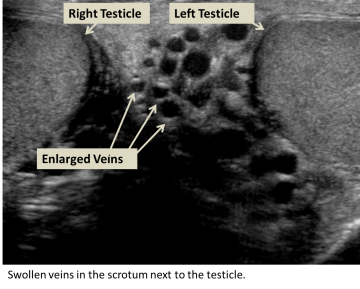

A varicocele is an abnormal enlargement of veins in the scrotum. Normally, veins bring deoxygenated blood back to the heart, but when the blood cannot flow properly, blood builds up and causes veins to dilate. Disruption in blood flow can result from problems with or missing valves in the veins or blockage of the veins. Blockage of the veins can be caused by blood clots, tumors, enlarged lymph nodes, or compression between other blood vessels. Varicoceles are similar to varicose veins, which occur in the legs.

The physician will perform a physical exam, but if the varicocele is small, it can be difficult to see or feel. During the exam, you will be asked to stand and hold your breath while bearing down, also known as the Valsalva maneuver, as the physician feels the scrotum for enlarged veins. An ultrasound may also be ordered to see the veins and testes sizes.